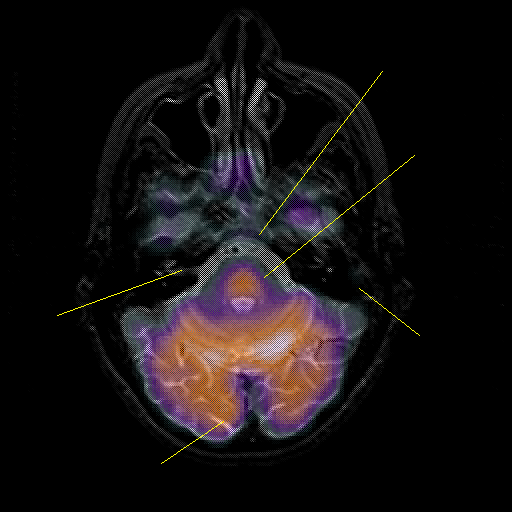

overlay : Slice 15

Slice 15

Pointers

Labeled